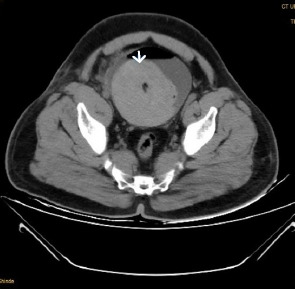

Abstract Image